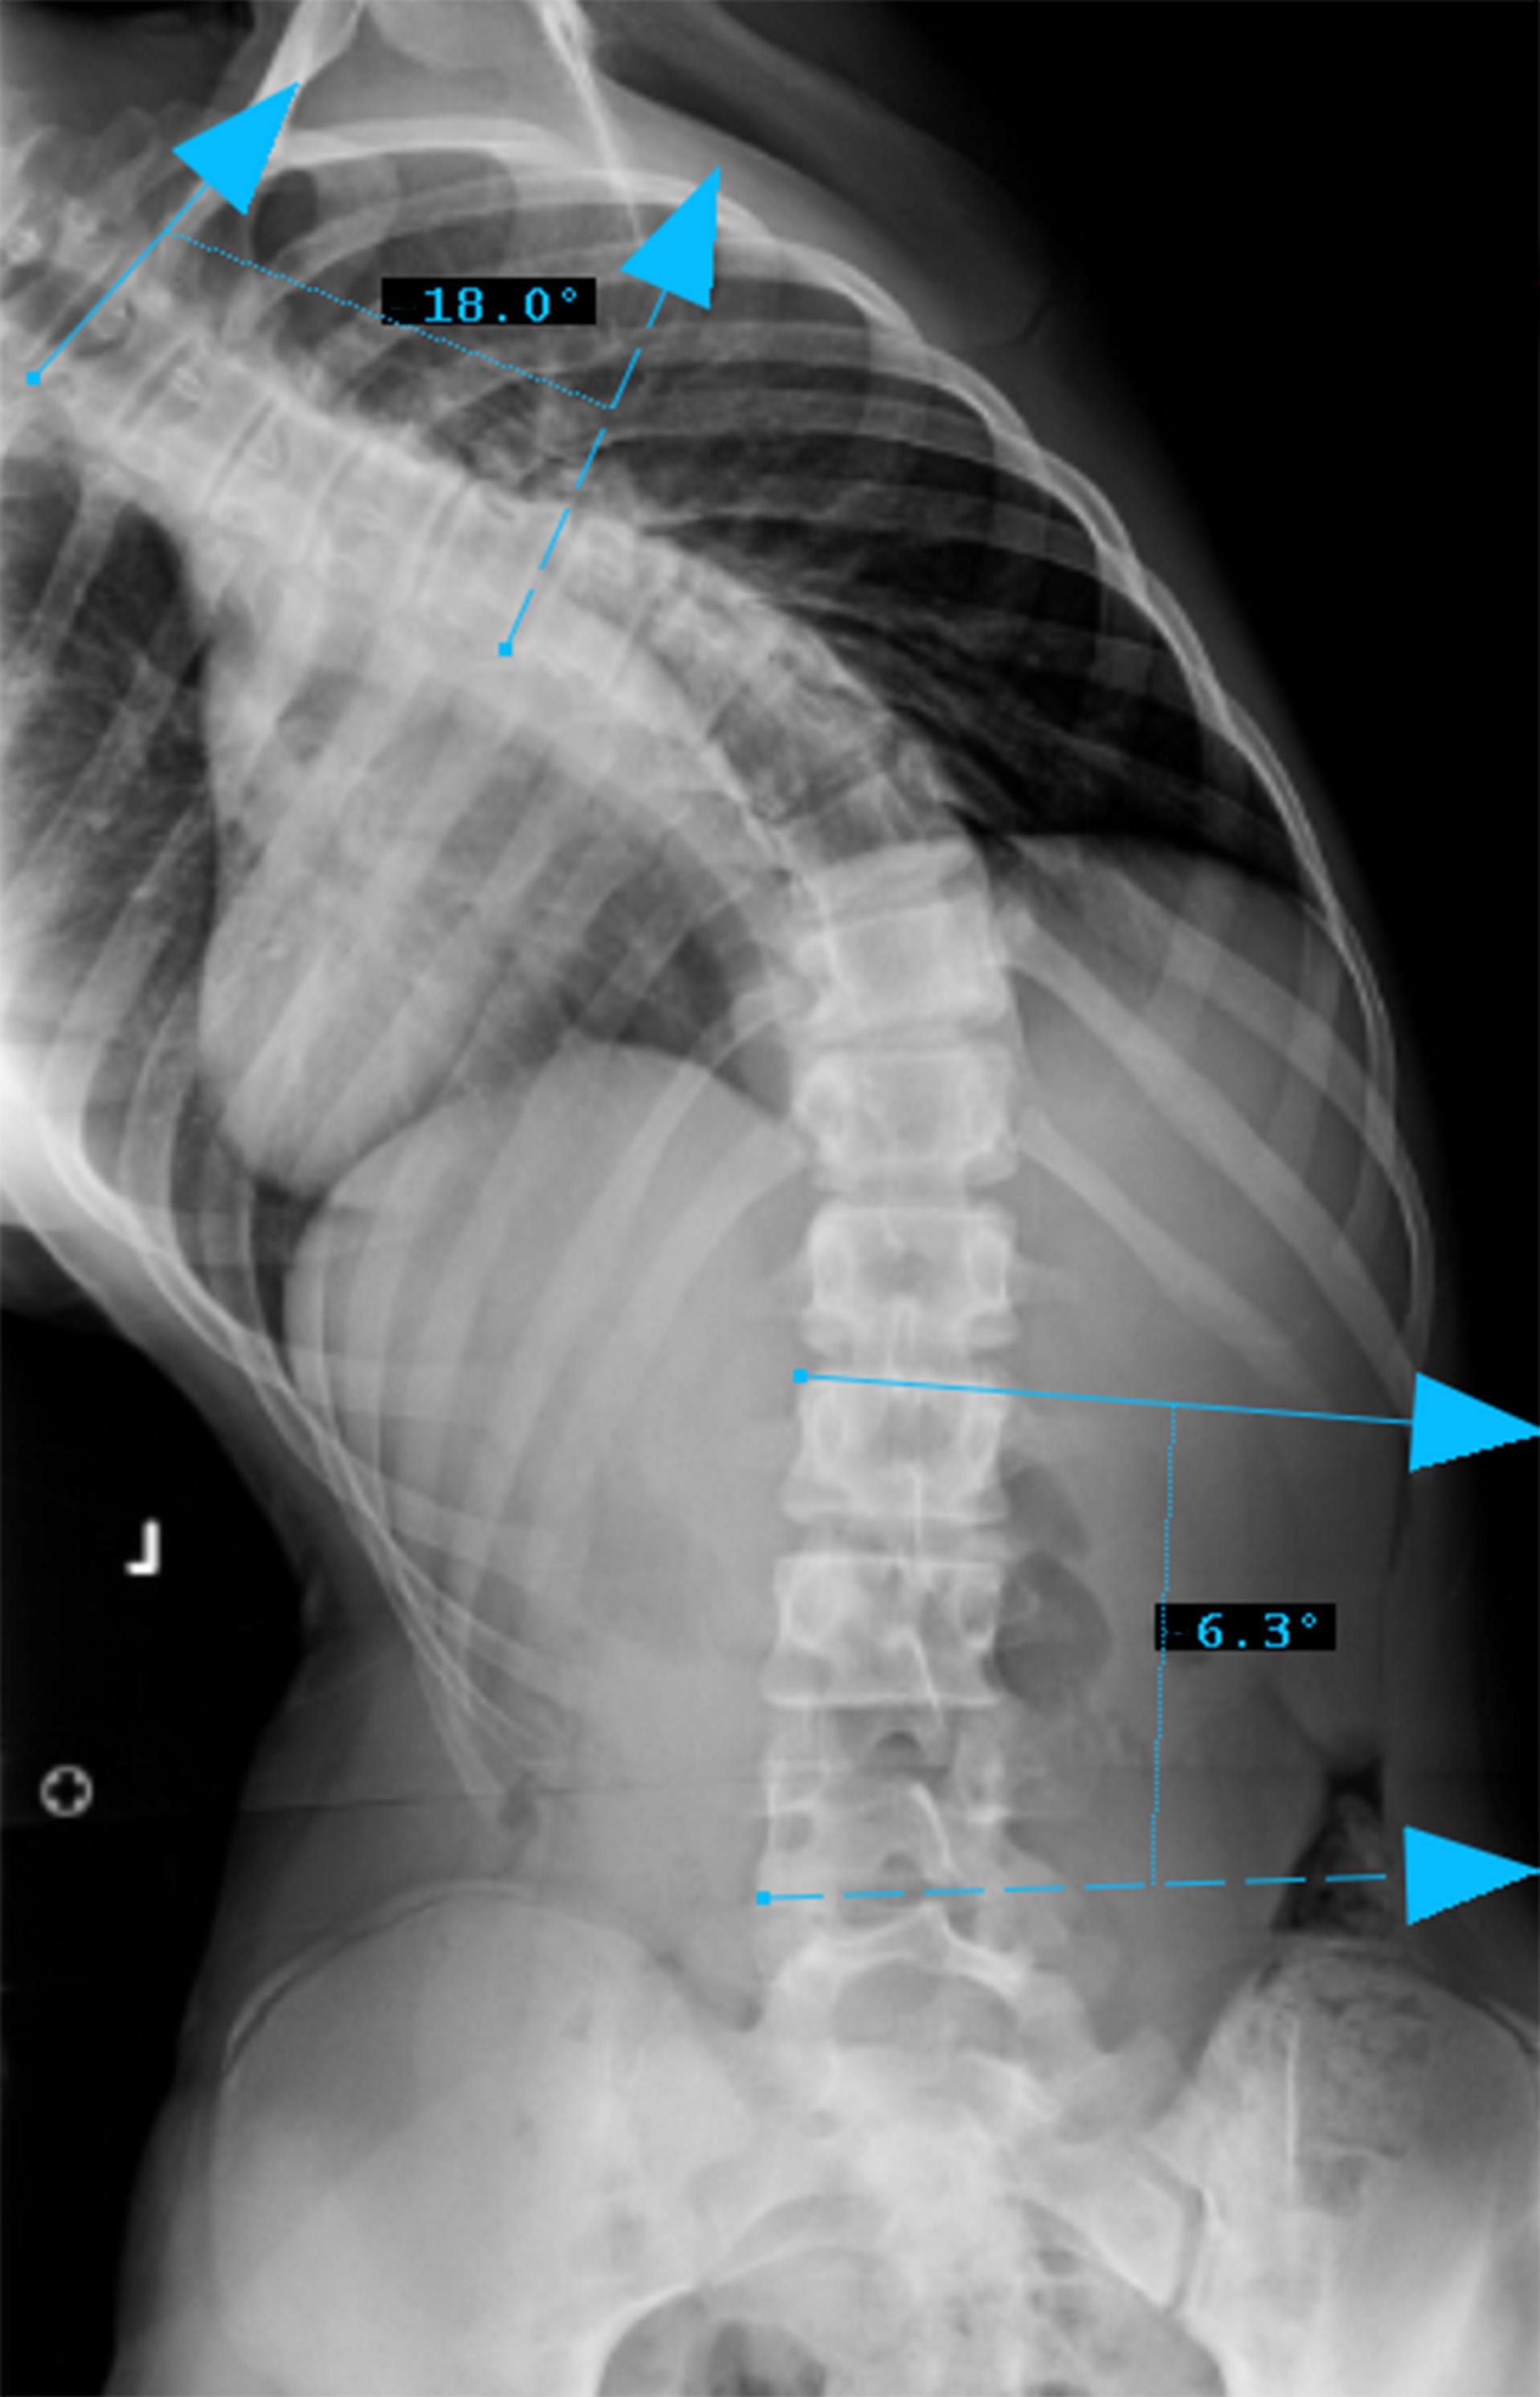

Preop RIGHT Bend